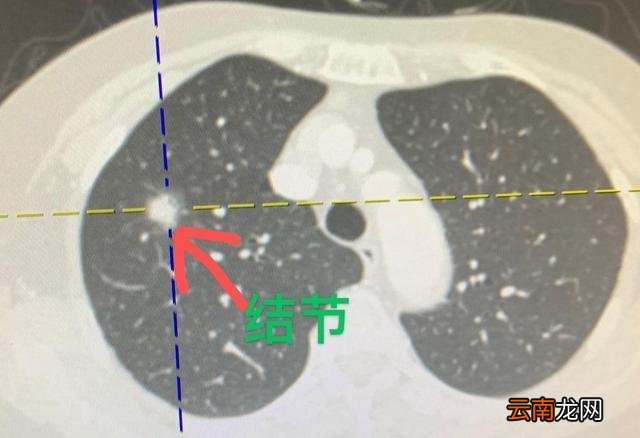

肺结节一般分3种:

1、结核球 ,

2、炎性假瘤或球型肺炎 ,

3、周围型肺癌 。

根据描述:右上肺类圆形结节影 , 边缘光滑 , 肺门及纵膈未见明确肿大淋巴结 , 可除外周围型肺癌

很重要的一点你没有说:结节的密度 。 。 。 。

如密度均匀或有钙化 , 就考虑为良性的了 , 周围是否有卫星灶?结合临床是否有结核病史及近期是否高烧、咳黄痰可明确诊断为结核球还是炎症!

肺部结节时患者的早期症状大多轻微 , 甚至没有相应的临床表现 , 仅在体检时发现zhidao 。 在这种情况下 , 如果发现肺部结节 , 应进行规范的评估 , 如进行肺部高分辨CT检查 , 根据结节的形态及大小 , 决定随访或治疗回方案 。

当结节表现为双肺分布毛刺、分叶 , 及其他恶性肿瘤的征象时 , 应给予积极的干预查 , 从而及时治疗 , 避免病情延误 。

小结节灶可以见于肿瘤、炎症或者结核 , 不是全部都是考虑肿瘤的 。

建议您做一个CT看看肺部整体的情况 , 看看有没有淋巴结的异常 , 建议您可以吃点抗生素观察一阵 , 看看小结节灶有没有缩小 , 如果缩小的话是可以考虑是炎症 , 如果没有缩小的话还需要继续检查!